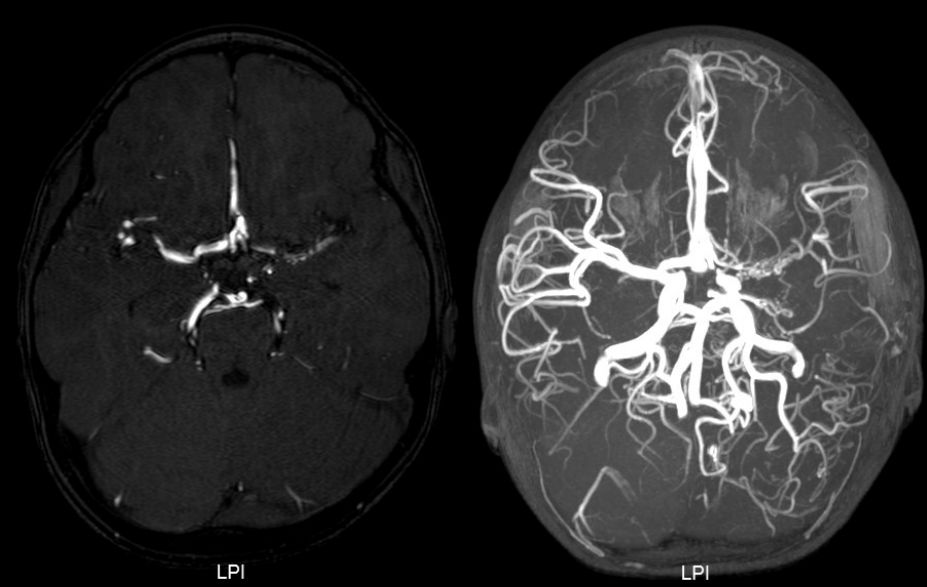

查头颅MRI提示:左侧鞍上可见两处结节状异常信号影,病变内信号不均匀,周围可见扭曲血管流空影,增强后明显强化,血管畸形伴出血可能(图2)。

图2. MRI提示鞍上及外侧裂区多发类圆形结节病灶,强化明显,边界清。